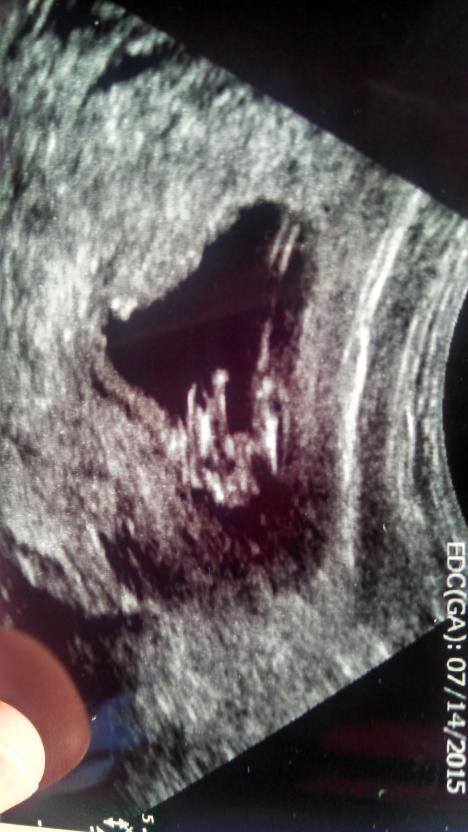

12 weeks 2 days

Too early to use a potty shot. Do you have any other pictures? x

Just of the babies head and arms. That's about it:( but I see 3 lines I was leaning towards a girl but I know it's kinda early. But I'll was seeing what you guys thought.

Even though it's early I would be leaning towards a girl. Congratulations on baby.

I see the lines BUT they are too high off the body. It COULD be swollen labia but wayyy too soon to go off a potty shot. 15ish weeks is when you can go for those sometimes at 14 but 15 is safe.

With my last pregnancy it was obvious it was a boy from my 12+2 potty shot from my nt scan. Yours looks very girly :)